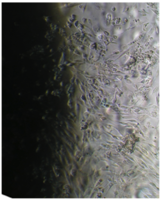

Исследование проведено на первичных культурах дермальных фибробластов и мезенхимальных стромальных клетках человека 4-12 пассажа.

Культуру дермальных фибробластов получали из кожно-мышечной ткани, а культуру мезенхимальных стромальных клеток – из фрагментов крыши черепа абортусов сроком 6-10 недель методом первичных эксплантатов (рис. 1, 2).

Клетки культивировали в стандартных условиях в термостате Sanyo – Incubator MIR-262 при температуре 37°С в среде МЕМ с 10% эмбриональной телячьей сыворотки в пластиковых культуральных флаконах Orange Scientific (производство Бельгии), Corning (производство США) площадью 25 и 75 кв. см. Тестирование производили в культуральных чашках Петри Sarstedt диаметром 3 см (рис. 3).